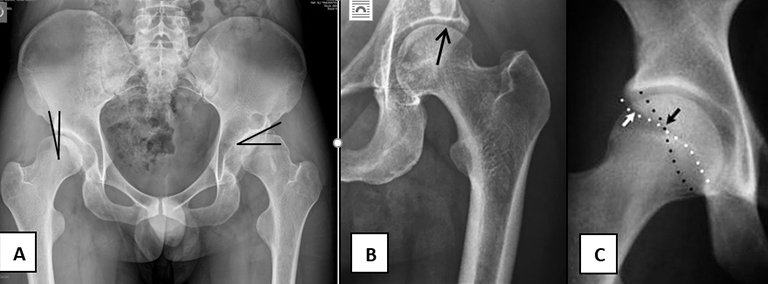

Figura 1

A- Hombre de 27 años de edad, con displasia bilateral de cadera, ángulo centro borde lateral disminuido e índice acetabular aumentado. Cadera derecha: medición ángulo de Wiberg. Cadera izquierda: medición del índice acetabular.

B- Cadera izquierda dolorosa en mujer de 42 años. Al medir no confundirse con la calcificación del labrum o los osteofitos laterales con el verdadero techo acetabular. El techo a medir termina en la flecha. La cadera es displásica.

C- Retroversión acetabular: pared anterior (blanco) y posterior (negro) se deben cruzar en el borde supero externo del acetábulo. Cuando lo hacen más distal, como en este caso, es el signo de entrecruzamiento positivo.

Figura 3

A- Varón de 34 años, con displasia de cadera izquierda. Angulo de Wiberg pre OP de 14°.

B- 4 años tras cirugía, con Wiberg 29°.

C- Mujer de 19 años de edad con retroversion acetabular. Se observa signo de entrecruzamiento positivo, silueta de pared posterior acetabular medial al centro de la cabeza femoral y espina ciática prominente.

D- 6 meses post cirugía. Entrecruzamiento negativo.